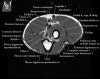

팔꿈치 관절의 MRI 단면 영상

4. MR Arthrography : Useful for evaluation of the collateral ligaments and cartilage surfaces.

5. Elbow Arthrography : UCL pathology in throwers, Osteochondral lesions and repair, Loose bodies